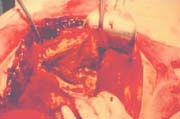

En la cirugía se encontró una peritonitis tabicada, con un gran quiste, de 30 cm de diámetro, que reemplazaba el lóbulo derecho del hígado, con membranas fibrinopurulentas en su interior, y quistes de 4 cm de diámetro en el lóbulo izquierdo del hígado.

Se realizó drenaje de la peritonitis, lavado peritoneal, destechamiento del quiste mayor y fenestración de los quistes pequeños (Figuras 3-6).

Figura 3. Quiste de 30 cm de diámetro que reemplaza todo el lóbulo derecho, sin tejido hepático visible, con paredes engrosadas y membranas de fibrina.